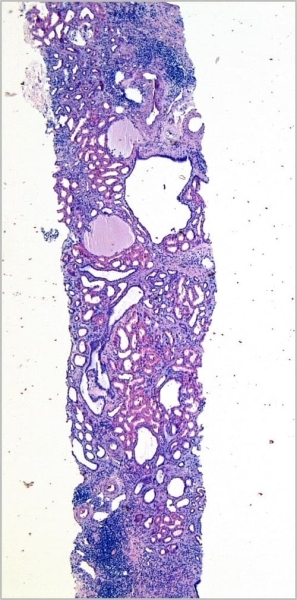

Фото 1.Приведу пример — заболевание у брата (13 лет) и сестры (9 лет) с неотягощенной наследственностью, у которых с раннего возраста отмечался упорный энурез. На фоне переносимой инфекции практически одновременно у детей ухудшилось самочувствие, и они были госпитализированы. На УЗИ были выявлены выраженные диффузные изменения в паренхиме обеих почек без значимого изменения их размеров.

Была выполнена нефробиопсия, которая показала у обоих детей схожие изменения в ткани почек, связанные с образованием множества канальцевых кист (см. фото 1) с выраженной круглоклеточной инфильтрацией и фиброзом стромы, атрофией канальцевого эпителия, утолщением и удвоением базальных мембран (в том числе неатрофичных канальцев) (см. фото 2).

Фото 2.